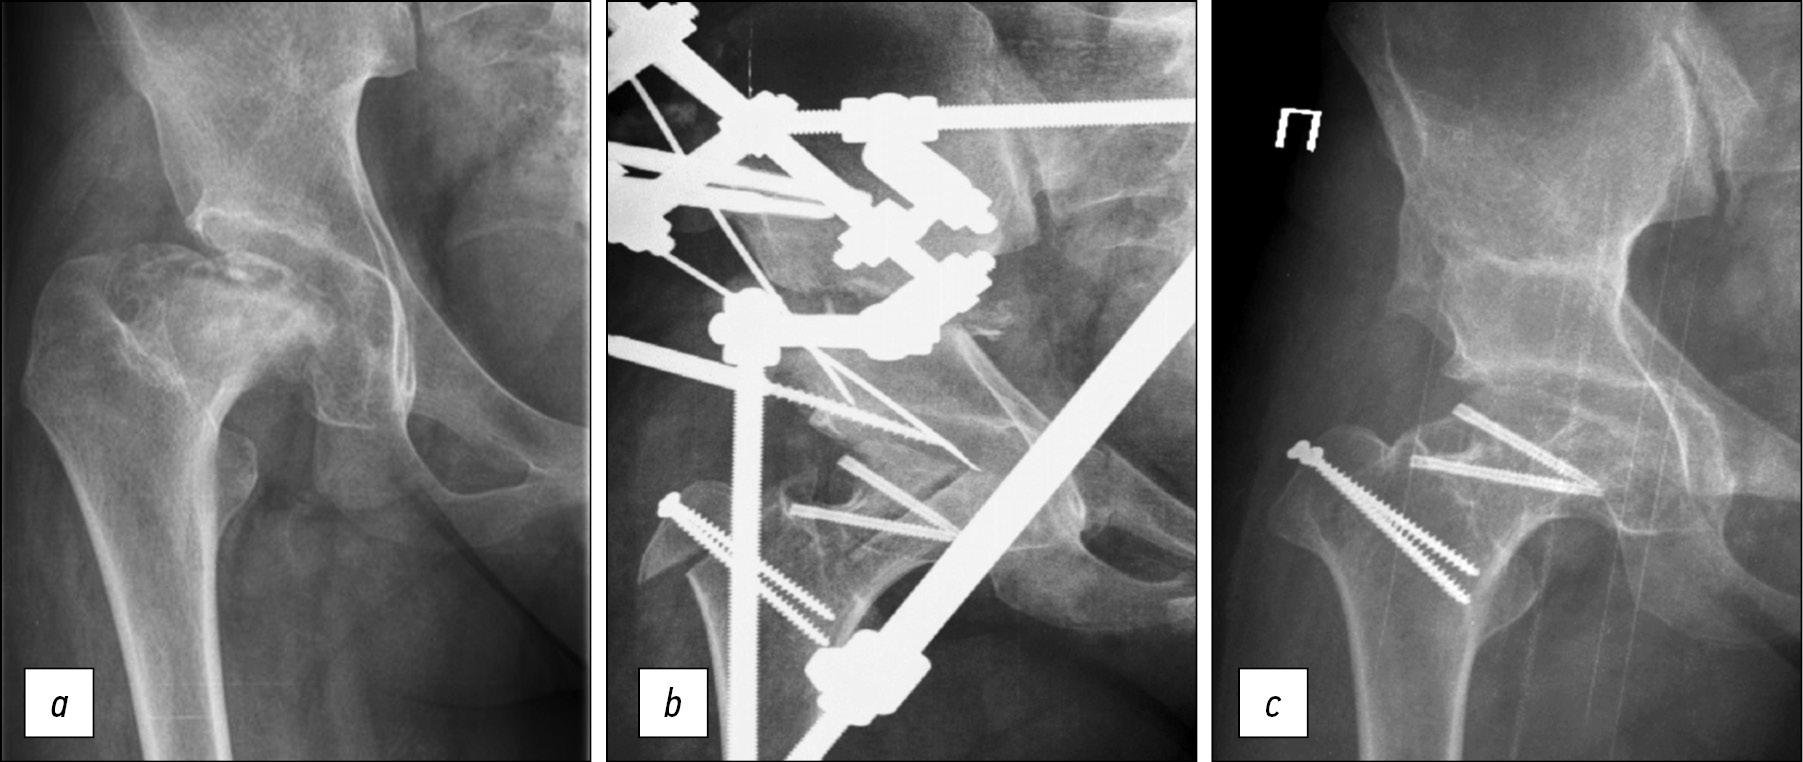

Рис. 2. Рентгенограммы пациентки 15 лет: a — до лечения: вторичный коксартроз I степени, ишемическая деформация головки и проксимального отдела бедра вследствие болезни Пертеса (ISH 1,8; ATD 0 мм), вторичная дисплазия вертлужной впадины (WBZ 22°), децентрация головки правого бедра (ICAS 0,8, AHI 0,65); b — в процессе лечения: остеотомия таза, хирургический вывих бедра, уменьшающая остеотомия головки бедра; c — через 3 года: ATD 10 мм, WBZ 0°, AHI 0,95

Fig. 2. Radiographs of a 15-year-old patient: a — before treatment: secondary coxarthrosis of the first degree, ischemic deformation of the head and proximal femur due to Perthes disease (ISH 1.8, ATD 0 mm), secondary dysplasia of the acetabulum (WBZ 22°), decentration of the head of the right hip (ICAS 0.8, AHI 0.65); b — during treatment: pelvic osteotomy, surgical dislocation of the hip, reducing osteotomy of the femoral head; c — after 3 years: ATD 10 mm, WBZ 0°, AHI 0.95